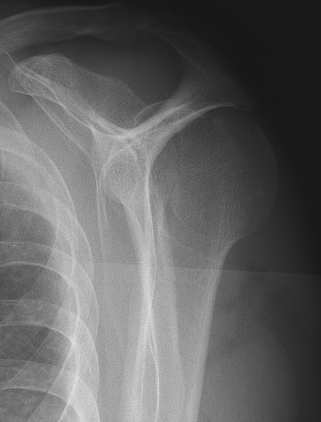

Posterior shoulder dislocation

Posterior shoulder dislocations